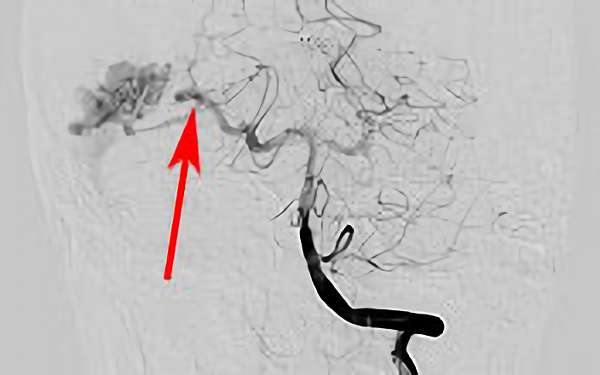

No.1620 手術前